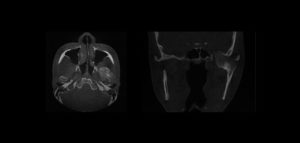

Se sabe que la tomografía computarizada de haz cónico (CBCT) produce exploraciones tridimensionales de la dentición, las estructuras duras maxilofaciales y la relación de las